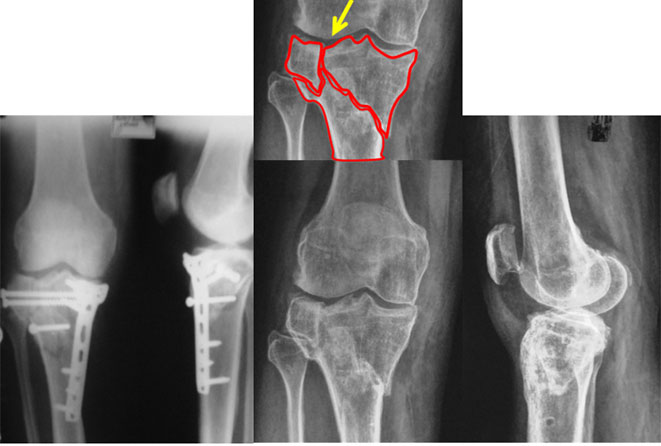

| This 43 year old gentleman had an accident about one & a half years back. He presented to us with pain in the right knee. The plate & screws had been removed about 2 months prior to his visit here. The new x-ray showed malunited fracture (fracture united in wrong position) of the upper tibia as shown in the picture above – the red lines show the fracture lines with the step (yellow arrow) in the articular portion of lateral condyle. |

An intra-articular osteotomy was performed. In this procedure the fracture is recreated along the original fracture configuration and then it is fixed in the corrected and desired position. In this instance the fixation was done using Locking Plate (the screws lock with the plate, providing additional hold & stability) and cancellous screws. |